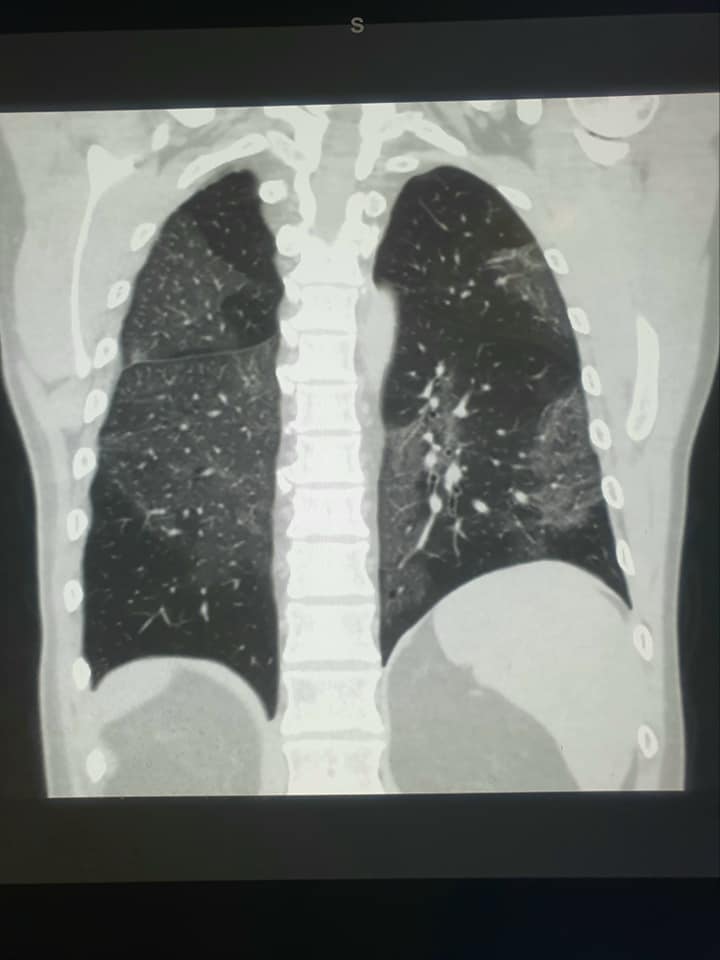

Un caso di polmonite da Covid

All’ospedale di Crema è presente un nuovo caso di grave polmonite da coronavirus. A darne notizia il radiologo Maurizio Borghetti, che dall’inizio della pandemia informa, tramite social, amici e concittadini sull’andamento del contagio.

Borghetti ha aggiunto nel suo post che il paziente ha 54 anni, non è vaccinaoto e che la polmonite gli impedisce di respirare. “I colleghi Clinici e Rianimatori avranno il loro bel da fare per tirar fuori dalle “pettole” la persona in questione”.

“Inevitabile il suggerimento ai (pochi) che ancora si son dimenticati di farlo, di andare a togliersi il pensiero invece del respiro… tirando su la manica della maglietta all’hub vaccinale più vicino”.